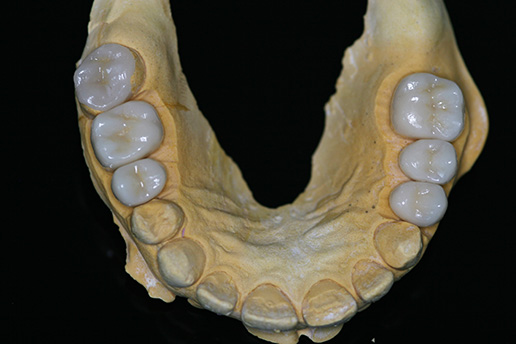

Full mouth rehabilitation of the patient with sorely worn dentition with the use of CEREC® CAD/CAM system Streszczenie W pracy przedstawiono opis zastosowania systemu CEREC® oraz technologii CAD/CAM przy projektowaniu i odtwarzaniu utraconej wysokości zgryzu. System CEREC® ze względu na ponaddwudziestoletnią obecność na rynku jest – zgodnie z opinią wielu klinicystów – najbardziej zaawansowaną technologią…